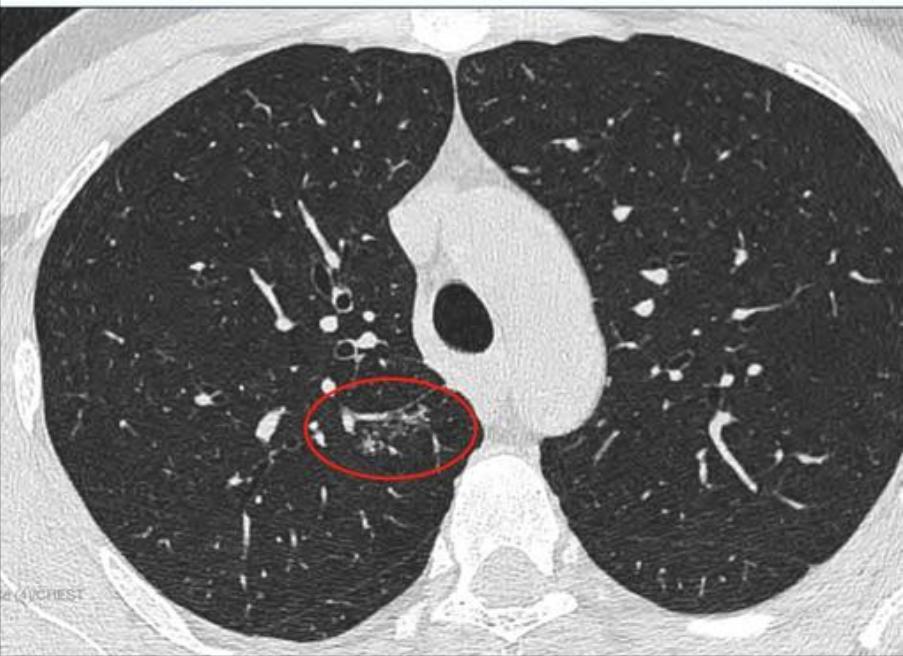

这是11月15日的CT图像与上次(7月29日)CT图像对比图:

再发一张:

辛苦主任,您看一下,结节虽然缩小了,还有1.7*0.9 CM,其他俩肺叶还有陈旧性病灶,应该继续服用拜复乐和夏枯草吗?8月份查过:男性肿标9项、过敏源检测(总IgE)、鳞状上皮细胞癌相关抗原、GM试验、隐球菌抗原、1,3-β-D葡聚糖 都是阴性,在正常范围内。就是结核感染T细胞还没查,您看是否需要查一下?主任辛苦您了,谢谢您!